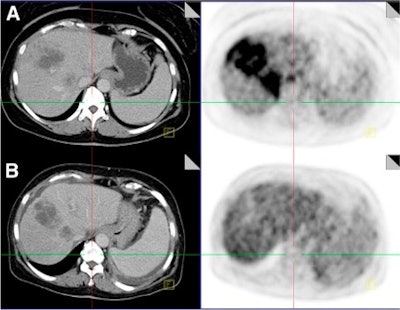

| CT images (left) and fused PET/CT images (right) were taken before therapy (A) and after therapy (B) and show large liver metastases. SUVmax decreased 273% after radioembolization, indicating therapy response, compared to tumor size measured by CT, which did not change significantly. Image courtesy of JNM. |

The study also showed that 22 participants (51%) responded favorably to therapy, while 21 (49%) did not fare well after treatment. Of those 21 women, seven (33%) experienced progressive disease based on the change in SUVmax. Therapy response based on SUVmax correlated significantly with survival after SIRT, with a median survival of 65 weeks for subjects who responded well to therapy, compared with 43 weeks for those who did not respond well after therapy.